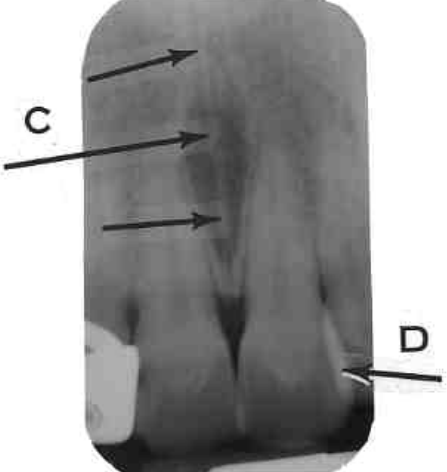

30. What is shown by arrow C?

31. What arrow shows?